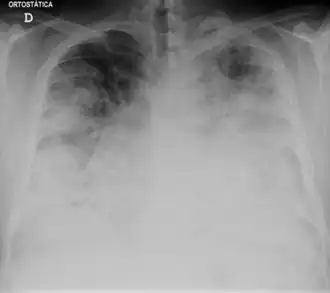

Différents stades de la maladie. Radiographie thoracique (A) et une tomodensitométrie à haute résolution (B) à la date d'hospitalisation. Tomodensitométrie du thorax une semaine après l'hospitalisation (C, D), d'un homme de 42 ans atteint d'une pneumonie grave causée par la Legionella pneumophila du sérogroupe 11a.

La radiographie du thorax peut montrer un infiltrat pulmonaire ainsi qu'un épanchement pleural. Les images peuvent persister un certain temps après la fin du traitement[26].